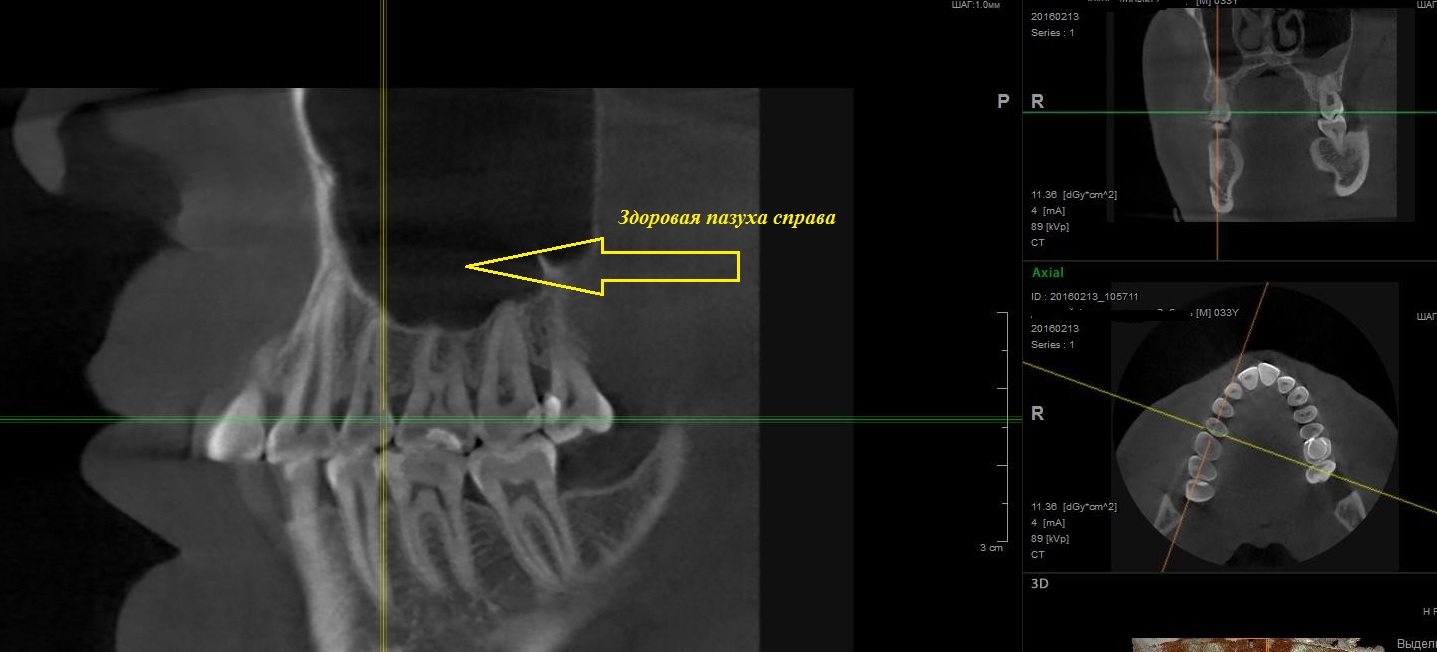

Рентгенологическое исследование

Рентгенологическое исследование является неотъемлемой частью диагностики заболеваний пародонта. Панорамные снимки позволяют оценить состояние костной ткани, определить наличие костных дефектов, степень резорбции альвеолярных отростков. Прицельные снимки дают более детальное изображение отдельных зубов и окружающих тканей. Рентгенологическое исследование позволяет оценить степень тяжести заболевания и прогнозировать его дальнейшее развитие.